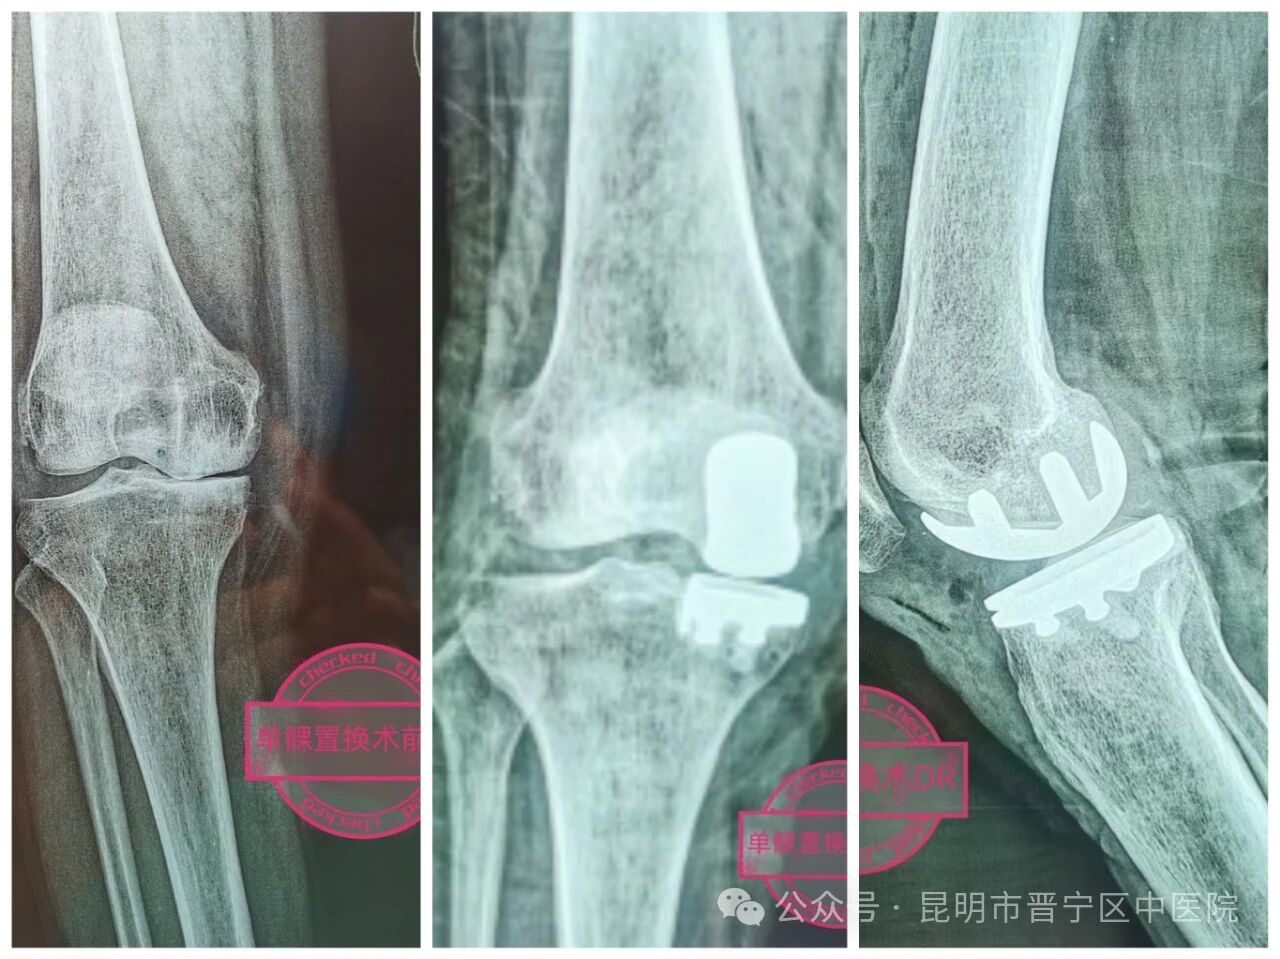

术前DR摄片 术后DR摄片

近日开展的膝关节微创置换术(UKA)是膝关节骨性关节炎阶梯治疗终末期,保守治疗效果不佳。通过手术保留部分骨质和前后交叉韧带,适用于膝关节骨性关节炎终末期,以膝关节骨性关节炎内侧、单侧间室骨质损伤,患者通过微创手术,现已负重行走活动,自行独自行走出院。